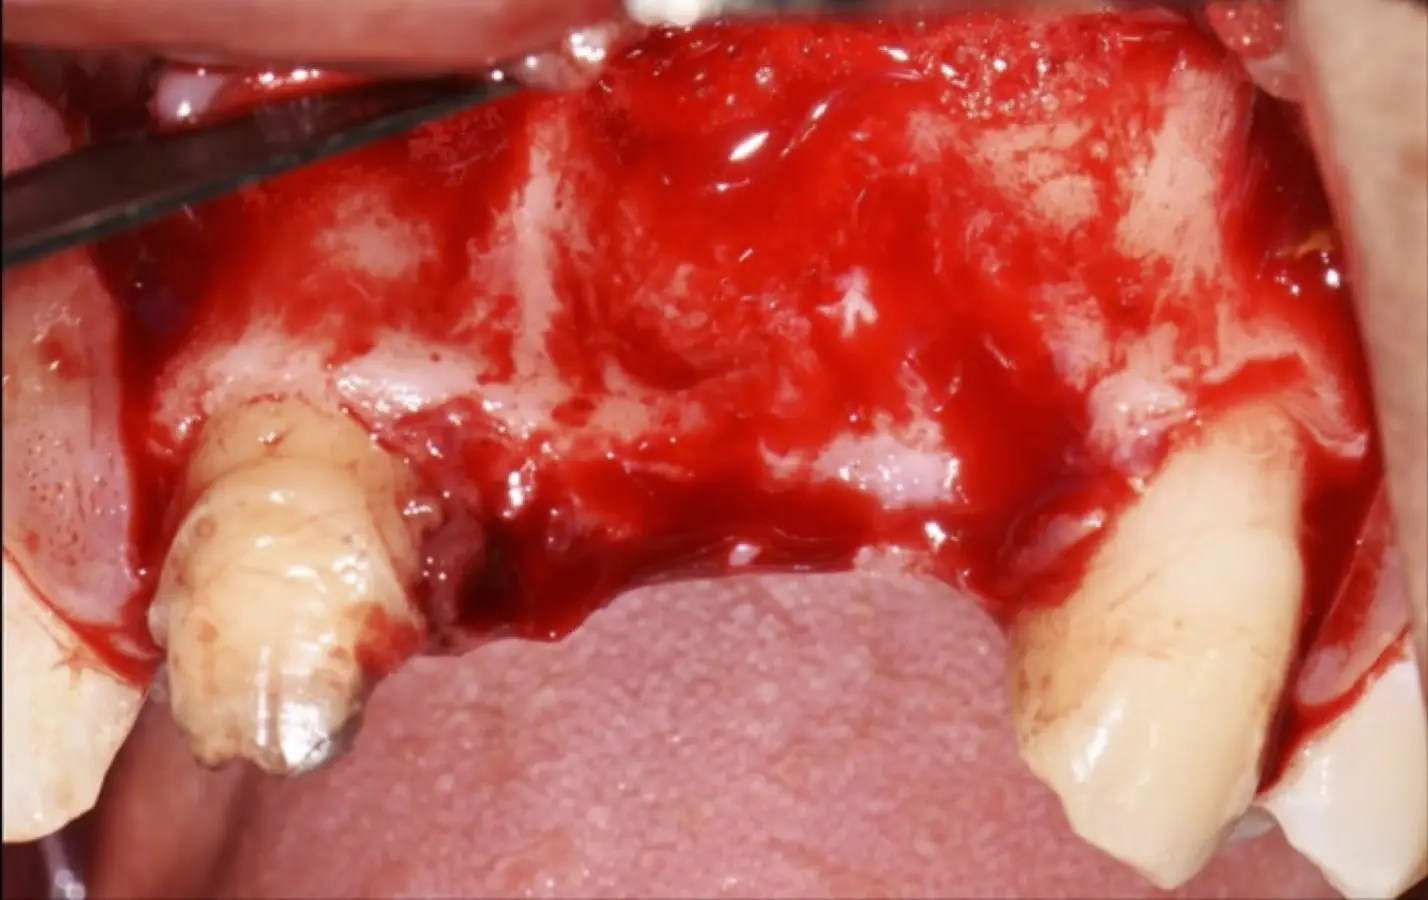

En las imágenes superiores se aprecia una reconstrucción de reborde con injertos en bloque previo a la planificación de implantes; en las imágenes inferiores, se observa la deficiencia vertical del reborde óseo y el tratamiento realizado con el piezoeléctrico.

Figura 18. Vista clínica en la que se evidencia la deficiencia horizontal severa del reborde alveolar.

Figura 35. Decolado a espesor total sobrepasando la línea mucogingival (a, b).